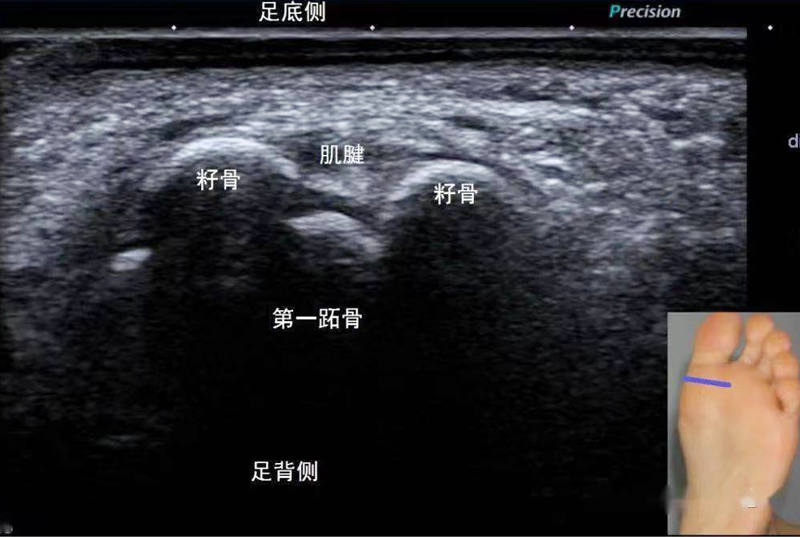

經(jīng)過對王姐的腳部軟組織

及周圍結(jié)構彩超檢查

發(fā)現(xiàn)右足第一跖趾關節(jié)

足底側(cè)(跖側(cè))

兩塊籽骨的

骨皮質(zhì)表面毛糙

周圍軟組織明顯增厚、水腫

并且血流豐富

符合足底籽骨炎的超聲表現(xiàn)

該籽骨位于咱人體足部

第一跖趾關節(jié)足底內(nèi)側(cè)

分為左右2塊

包埋在拇短屈肌肌腱內(nèi)